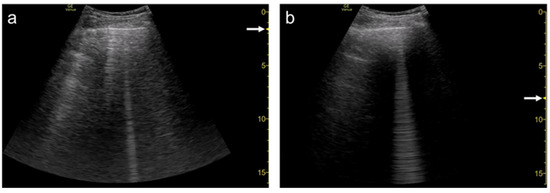

3.1. Spatial Compound Imaging